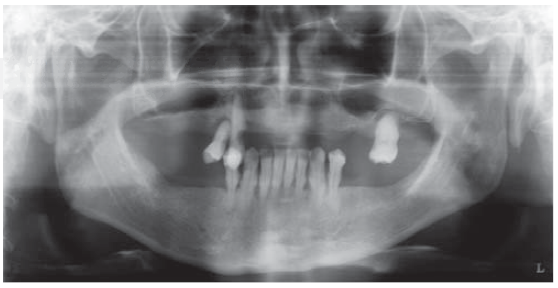

Examen radiográfico

A la evaluación radiográfica se observó reabsorción ósea horizontal generalizada, neumatización de ambos senos maxilares, lesión cariosa en pieza 1.3, lesiones radiolúcidas a nivel del periápice de piezas 1.3, 1.4, 2.6 y 4.4 (Figura 1).

Mediante la información obtenida en el examen clínico y radiográfico se determinaron los siguientes diagnósticos: periodontitis crónica generalizada severa, caries en pieza 1.3, abscesos dentales en piezas 1.3, 1.4, 2.6 y 4.4; y edentulismo parcial superior e inferior con atrofia del reborde alveolar superior neumatización de seno maxilar bilateral.

Evaluación tomográfica

Se indicó una tomografía computarizada Cone Beam para evaluar la disponibilidad ósea remanente con finalidad de colocar implantes. A la evaluación se evidenció que en el maxilar superior, a pesar de la reabsorción ósea generalizada, se encontró cantidad ósea suficiente para la colocación de implantes en sentido coronoapical. Por el contrario, en sentido bucopalatino no se encontró la cantidad ósea suficiente para una colocación de implantes de manera convencional (Figura 2). Por tal motivo, este maxilar correspondería a la clase III de deformidades de los rebordes alveolares de Seibert, por lo cual es necesario realizar procedimientos quirúrgicos adicionales que permitan la colocación mínima de seis implantes.

Figura 2 La CBCT mostrando reabsorción ósea horizontal generalizada, aunque verticalmente, suficiente hueso encontrado en sentido apicocoronal. De izquierda a derecha superior: área de la pieza # 1.1, 1.2 y 1.4. De izquierda a derecha inferior: piezas # 2.1, 2.2 y 2.4.

En cuanto al maxilar inferior, se evidenció un defecto óseo que compromete los aspectos vestibulares y linguales del hueso remanente a nivel de la pieza 4.2. Sin embargo, se encontró cantidad ósea suficiente para la colocación de cuatro implantes en la zona interforamen.